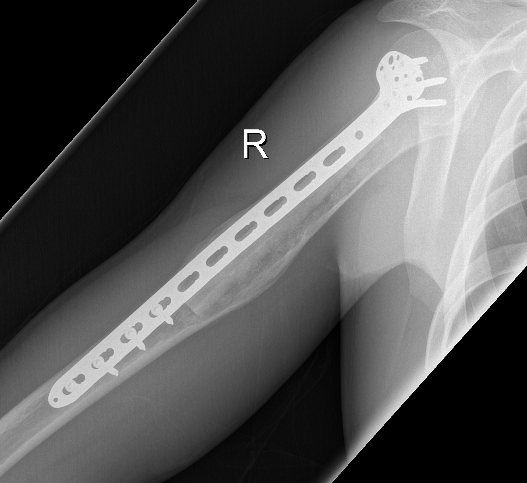

Options

- flexible nails humerus

Erol et al J Paediatr Orthop B 2017

- humeral simple bone cysts

- 37 curettage and bone graft

- 16 had addition of flexible nails

- 76% healing curettage and bone graft

- 100% healing with flexible nails

ORIF + fibular strut allograft

Jamshidi et al Int Orthop 2018

- 14 cases humerus UBC

- treated with locking plate + fibular allograft

- complete healing in 10, partial healing in 4